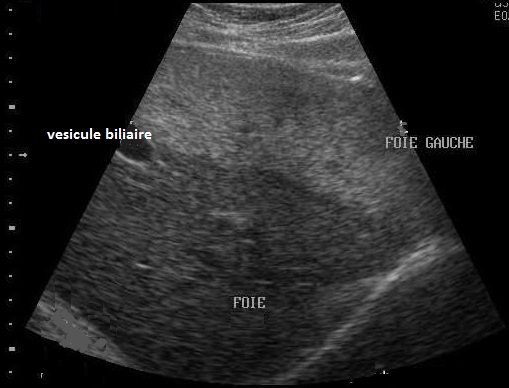

Image echographique d'une

steatose du foie . la parenchyme du foie est tres

hyperechogene Les vaisseaux du foie sont en

moindre visible |

Steatose du foie : La

parenchyme du foie est plus riche de echogene que le

rein . Et le bord du diaphragme en arriere est

en moins de visible . |